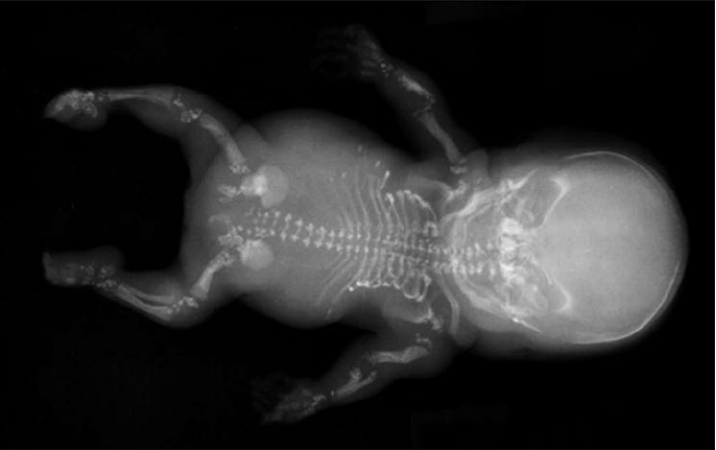

Conradi-Hünermannov syndróm (angl. Conradi-Hünermann syndrome) je názov pre vrodené genetické ochorenie, ktoré postihuje najmä kosti.

Choroba je spojená najmä s poruchami kostrového systému. Typický je nízky vzrast, krátke končatiny (mnohokrát nesúmerne) a krivá chrbtica. V koncoch dlhých kostí sa ukladá veľké množstvo vápnika. Objavujú sa aj isté abnormality v tvári, ako napríklad plochá tvár a prepadnutý koreň nosa. Postihnuté bývajú aj oči, u chorých častejšie dochádza ku vzniku šedého zákalu. Intelekt postihnutých je normálny, len výnimočne sa vyskytuje mentálna retardácia.

Choroba sa môže určiť na základe nálezu vyššie uvedených prejavov a po vykonaní špeciálneho genetického vyšetrenia, ktoré preukáže mutáciu príslušného génu.